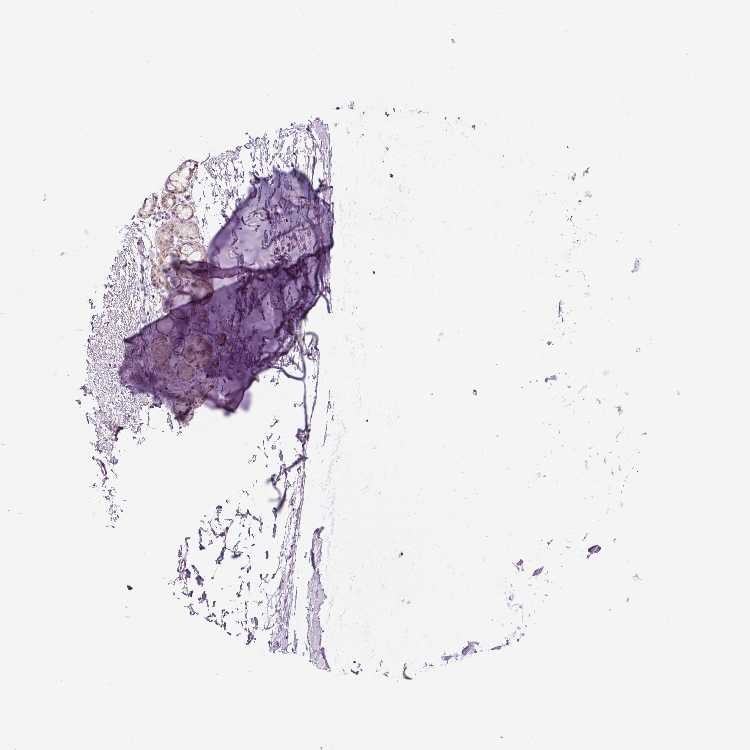

SOFT TISSUE 1 - Antibody stainingi

Antibody staining in the annotated cell types in the current human tissue is reported as not detected, low, medium, or high, based on conventional immunohistochemistry profiling in selected tissues. This score is based on the combination of the staining intensity and fraction of stained cells.

Each image is clickable and will lead to virtual microscopy that enables deeper exploration of all samples and also displays staining intensity scores, fraction scores and subcellular localization as well as patient and tissue information for each sample.

Antibody HPA052130

Chondrocytes Not detected

Fibroblasts Not detected

Peripheral nerve Medium